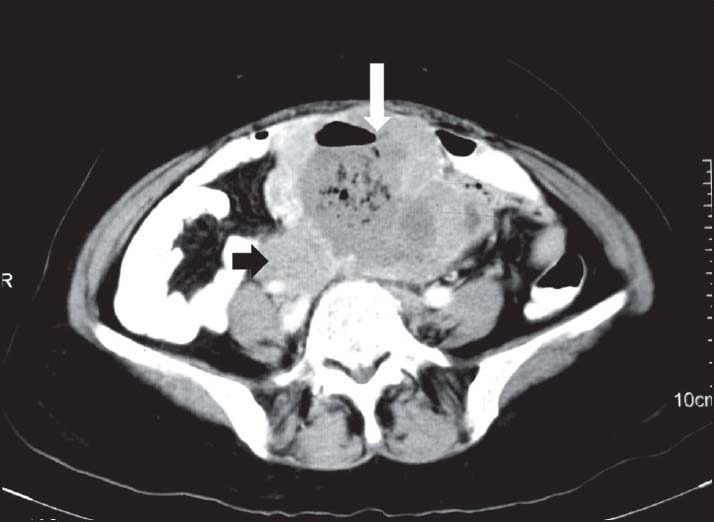

| Figure 5:Rectal gastrointestinal stromal tumors in a 49-year-old male — (a) barium enema spot image lateral view showing extrinsic impression on rectal wall (arrowhead) (b) axial contrast-enhanced computed tomography image showing heterogenously enhancing necrotic mass in pelvis (black arrowhead) displacing the urinary bladder (arrow) anteriorly

| Figure 5:Rectal gastrointestinal stromal tumors in a 49-year-old male — (a) barium enema spot image lateral view showing extrinsic impression on rectal wall (arrowhead) (b) axial contrast-enhanced computed tomography image showing heterogenously enhancing necrotic mass in pelvis (black arrowhead) displacing the urinary bladder (arrow) anteriorly

| Figure 4:Rectal gastrointestinal stromal tumors in a 50-year-old female contrast-enhanced computed tomography showing heterogeneously enhancing exophytic mass lesion arising from the rectal wall (arrowhead)

| Figure 4:Rectal gastrointestinal stromal tumors in a 50-year-old female contrast-enhanced computed tomography showing heterogeneously enhancing exophytic mass lesion arising from the rectal wall (arrowhead)